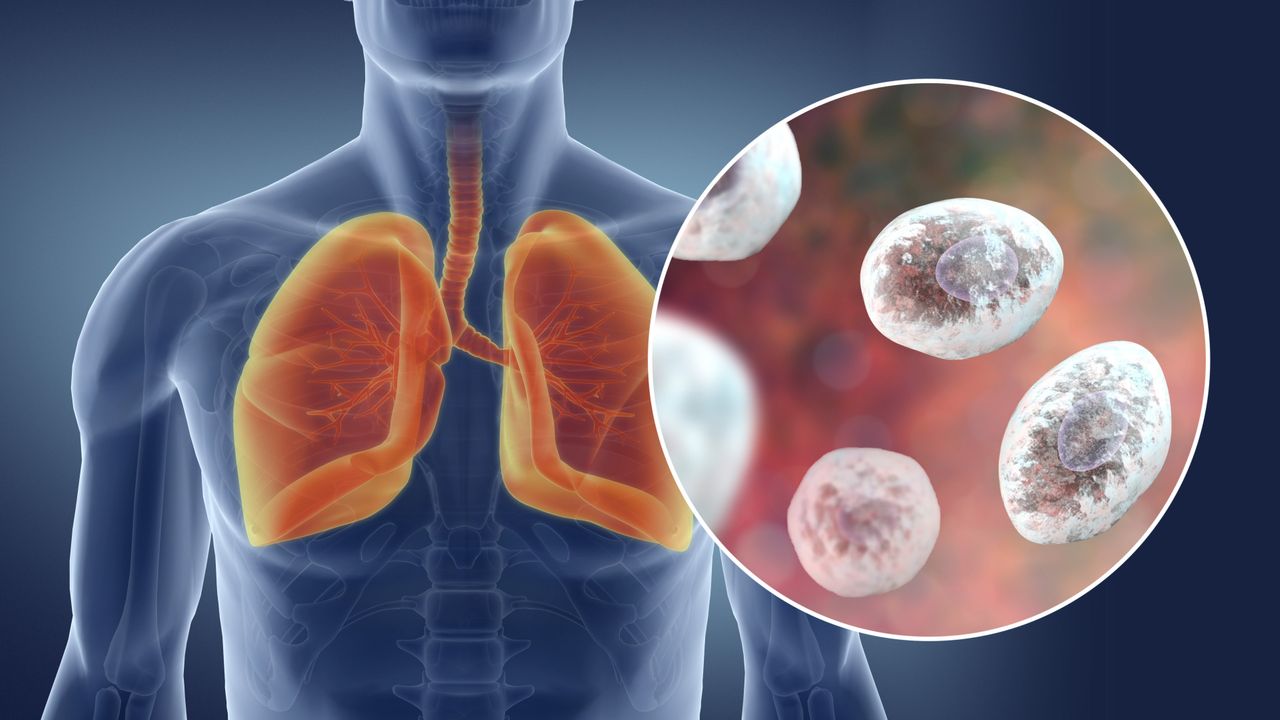

Pneumocystis Pneumonia (PCP)

This is a serious infection of the lungs. It's caused by a fungus called "Pneumocystis jirovecii." If you're healthy, you may have this fungus in your lungs and not even know it. But if you have a weakened immune system, it makes you very sick. It can be deadly.

How do you get infected? The fungus spreads from person to person through the air. You breathe it in, and it gets into your lungs. If your immune system can't fight it, your lungs become inflamed.